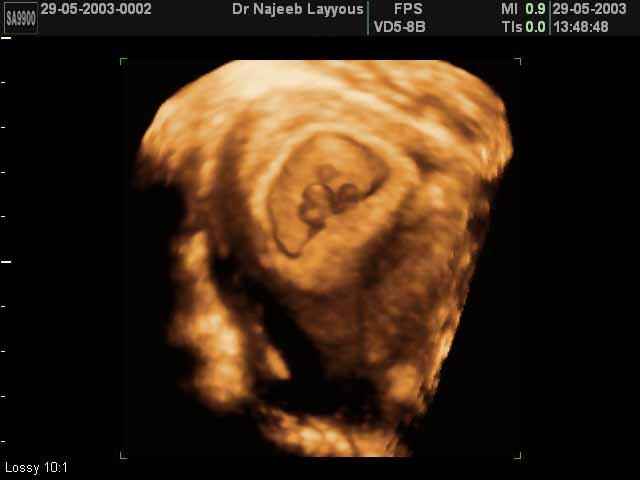

3D First Trimester Ultrasound Scan Photos